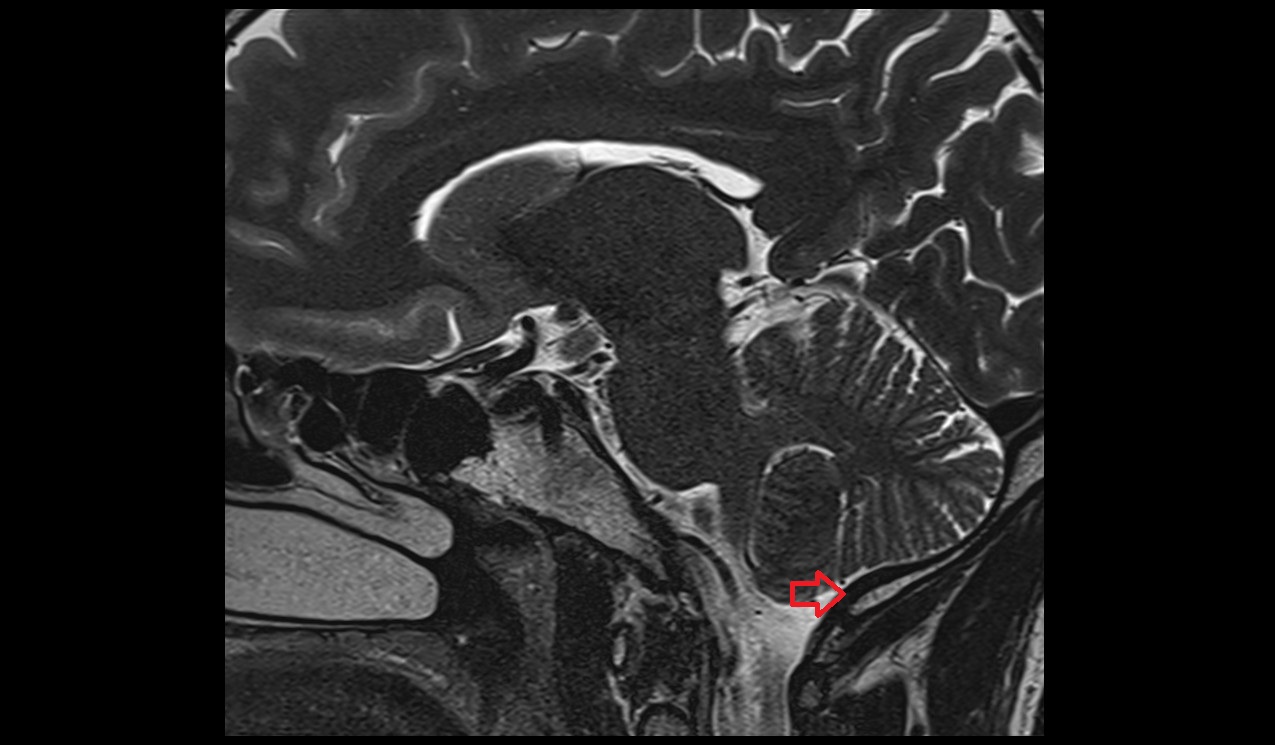

- Median aperture of fourth ventricle (foramen of Magendie)